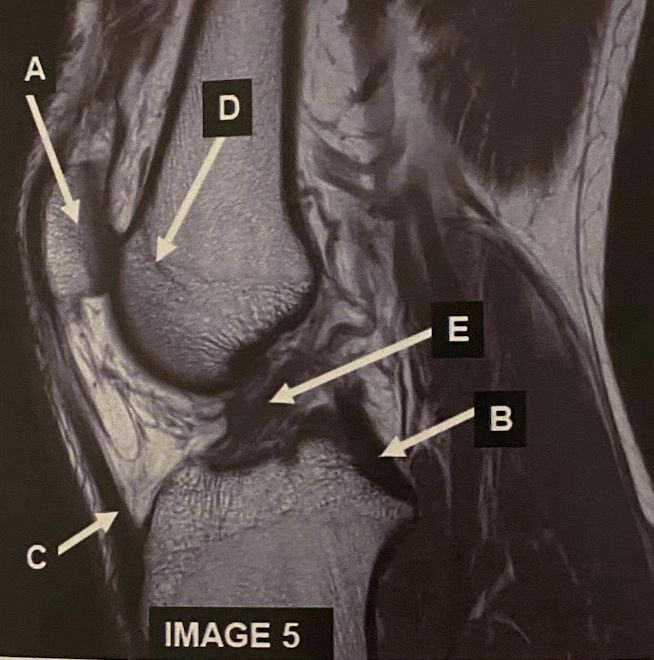

What anatomy does letter A demonstrate?

A

Patella

Q

What anatomy does letter B demonstrate?

PCL

22

What anatomy does letter C demonstrate?

Patellar Tendon

What anatomy does letter D demonstrate?

Femoral Condyle

24

What anatomy does letter E demonstrate?

ACL